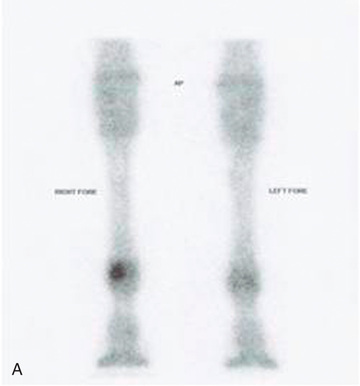

Consideration may need to be given to additional imaging for accurate diagnosis and prognosis. This would include ultrasonography as well as cross-sectional imaging modalities such as computerized tomography (CT), magnetic resonance imaging (MRI), scintigraphy, and further diagnostic testing. CT and MRI show the most detail in all structures, indicating actual soft tissue and cartilage within the foot. Modalities such as nuclear scintigraphy and thermography show problem areas to the bone and soft tissue, such as ligaments, tendons, and articular cartilage that are poorly imaged on radiographs (see Fig. 24.64).

It is beyond the scope of this text to discuss alternate modalities (Fig. 24.64) in this edition. Additional imaging, such as nuclear scintigraphy, infrared thermal imaging, and MRI, show more features for diagnosis but are considerably more expensive than imaging with the use of x-radiation.